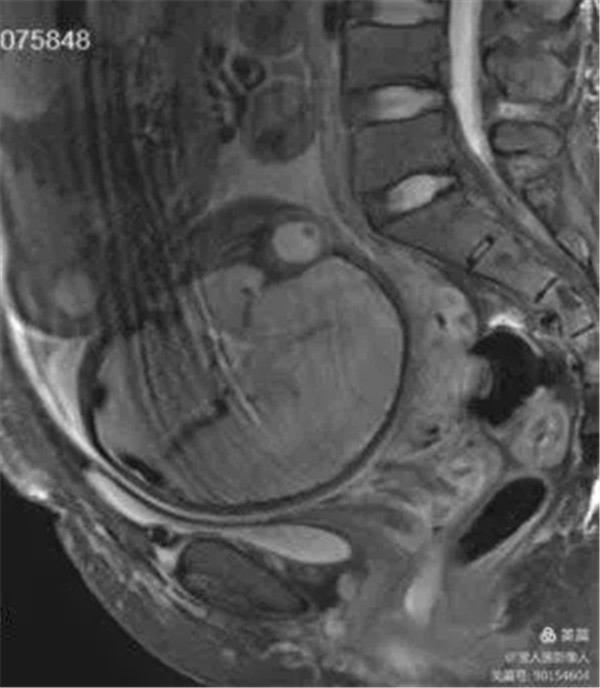

病例11:患者前置胎盘、血管前置、胎盘穿透性植入

图1,矢状位-显示胎盘与子宫后壁、宫颈、直肠关系